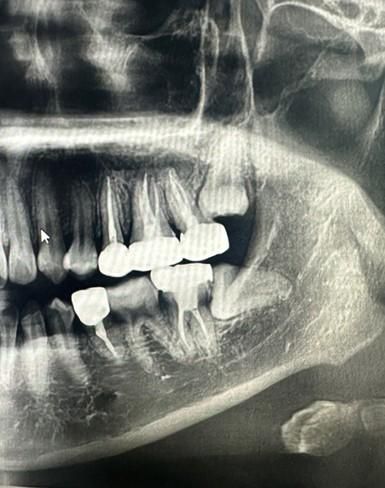

현재 왼쪽 가장 안쪽 어금니 (상단) 는 신경 치료 후 크라운을 씌워놓은 상태이고, 사랑니가 그 위에서 자라고 있는 중입니다. (작년 하반기 사진이며, 현재는 조금 더 곧게 내려왔고 크기도 큰 것 같습니다 사진이 없네요 ㅠ)

사랑니가 맹출하면서 염증이 생겨서 그럴수도 있고 신경치료한 치아의 뿌리쪽이 문제가 생겨서 그럴수도 있어 보입니다. 사랑니는 맹출 방향으로 봐선 발치를 추천드립니다. 발치후 그래도 문제가 해결되지 않으면 신경치료한 치아를 재신경치료(가능시)등을 통해 최대한 보존하는 쪽으로 상담받으시는것을 추천드립니다.

현재 상태에 대한 엑스레이를 찍어봐야겠지만, 두번째 큰 어금니가 문제가 생겨서 통증이 유발된다면 그건 빼야할 확률이 높고요.

사랑니는 상태에 따라 다른데 치아이식술이 가능할지는 온전히 사랑니 발치가 가능할지에 달려있습니다. 빼면서 손상이 있을 경우 쓰기 어렵습니다.

제가보기엔 두번째 큰 어금니, 사랑니 둘다 빼야 할 상황으로 보입니다.

사진에 보이는 사랑니는 특별한 이유가 없다면 발치를 하실필요는 없을것같습니다. 만약 사랑니 앞치아를 발치하고 사랑니를 교정적으로 당기면 대체는 가능할것같긴하지만 추천드리는 치료는 아닙니다.